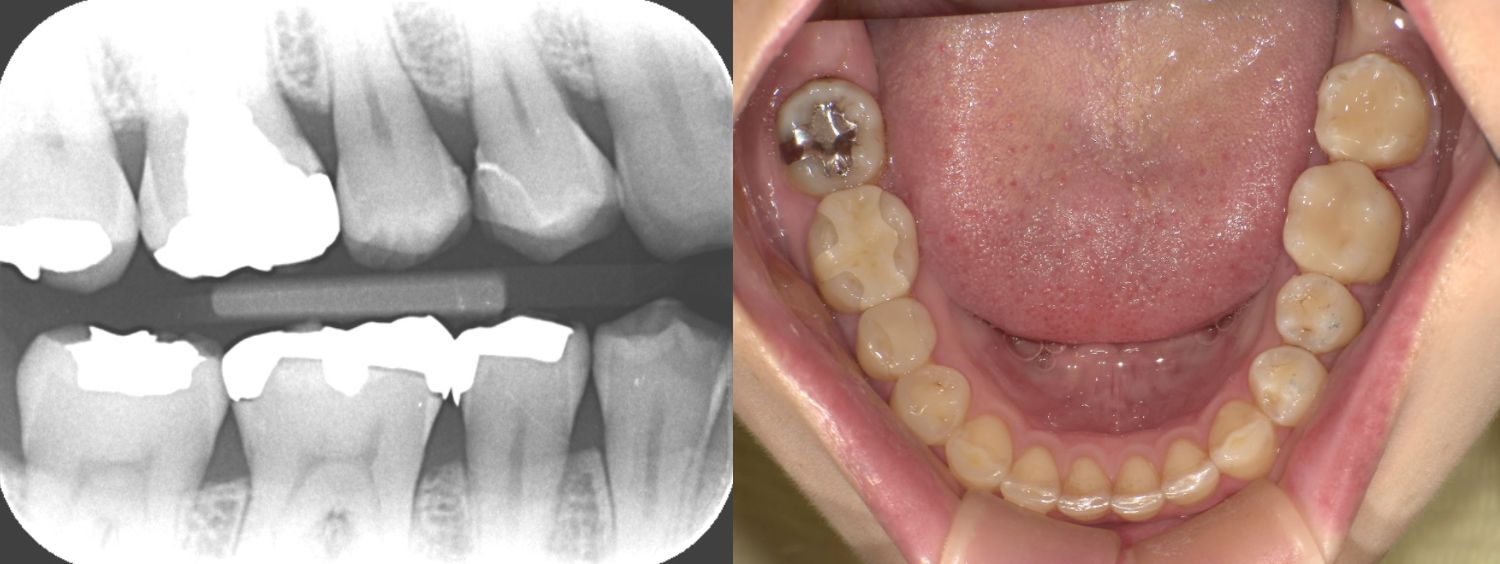

①術前

| 診断 | ①右上4う蝕 ②左上67う蝕 ③左下67う蝕 |

| 処置内容 (または主訴) | ①セレックインレー ②右上6セレックインレー 右上7CR ③セレックインレー |